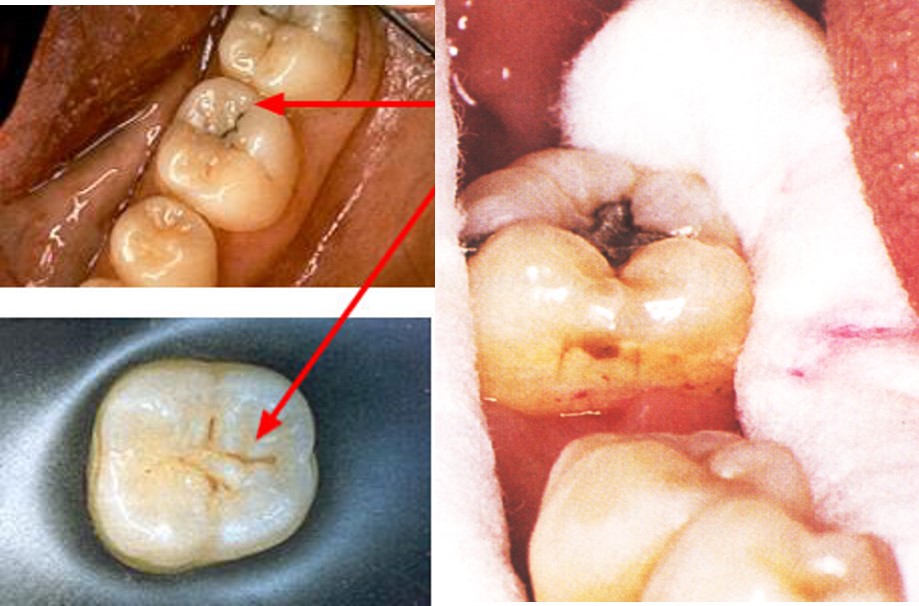

结果:牙硬组织破坏(图7.1-1)

图7.1-1 龋病